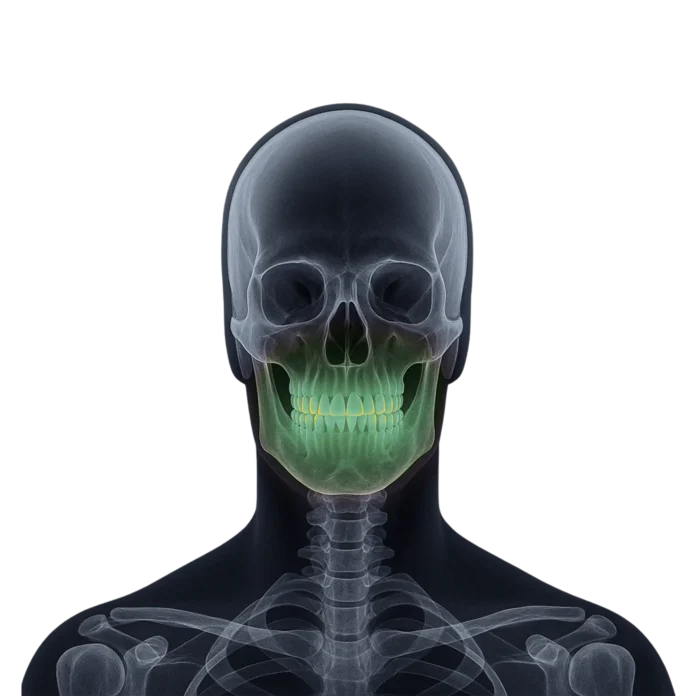

Tomografia dentară computerizată (CBCT) este o tehnologie avansată de imagistică care oferă imagini precise în trei dimensiuni ale maxilarelor și a structurilor orale.

Folosind radiografia dentară și radiografia panoramică vom avea imagini care ne vor ajuta in stabilirea diagnosticului, in schimb investigatia CBCT devine fundamentala pentru diagnosticarea și planificarea tratamentelor dentare, inclusiv a implanturilor și a procedurilor ortodontice, oferind o perspectivă detaliată asupra dintilor, maxilarelor și cavității bucale.

Utilizarea tomografiilor computerizate (CBCT) pentru a obține imagini tridimensionale ale maxilarelor și dinților sunt fundamentale în intervențiile chirurgicale de precizie și în tratamentele ortodontice, oferind medicilor stomatologi o vedere completă și detaliată asupra structurii dentare.